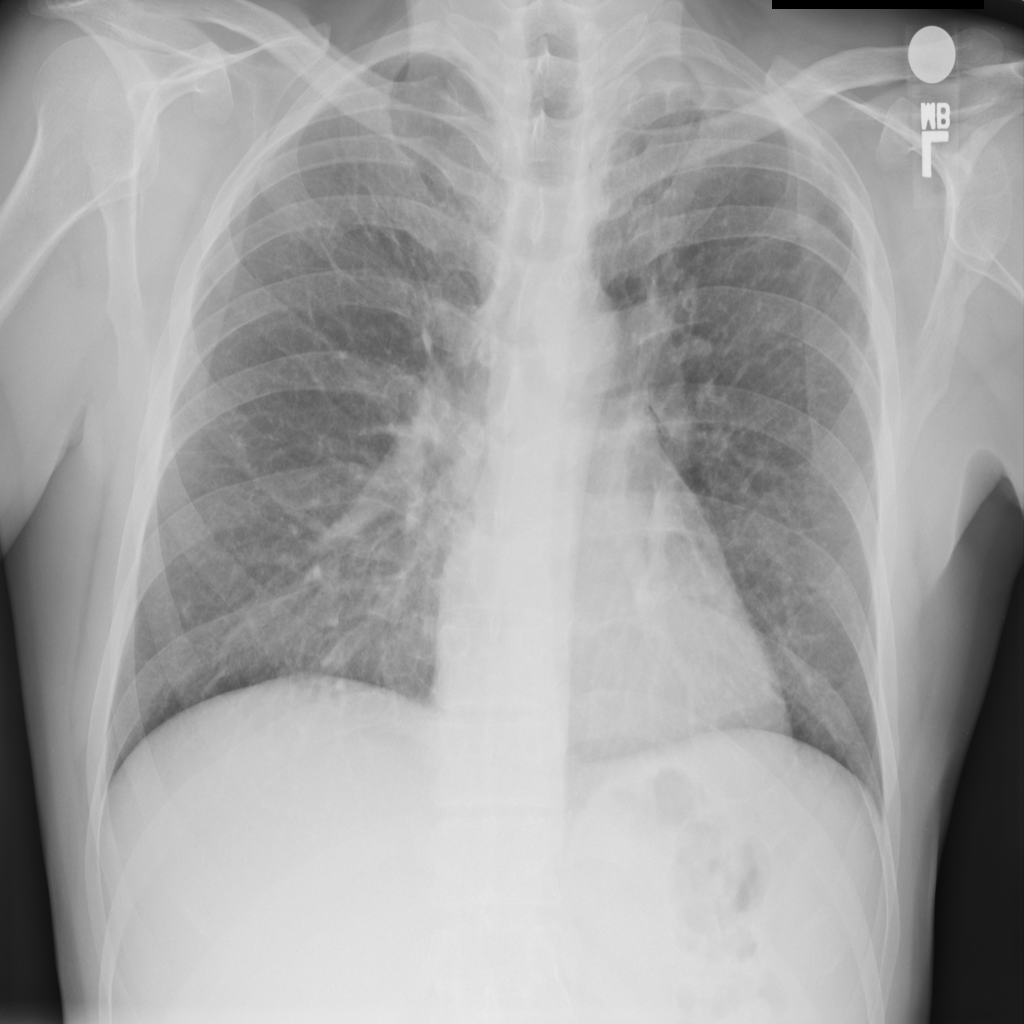

PAT-531A · IMG-006Consolidation

PAT-531A · IMG-006

PA